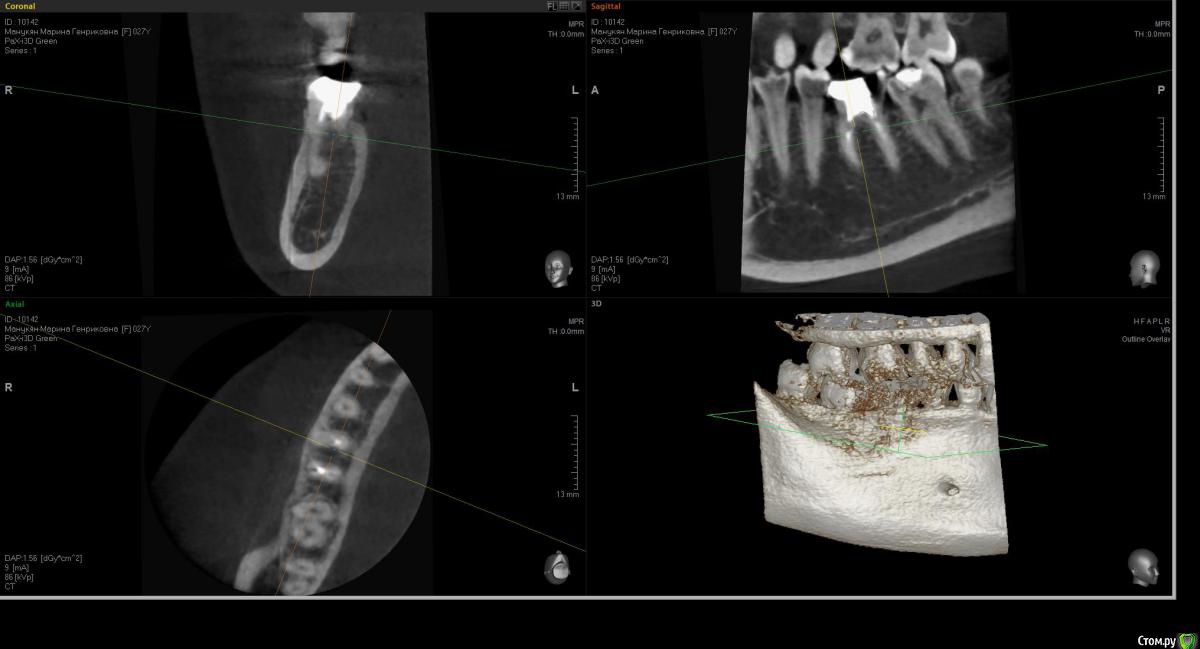

Kostoprav Опубликовано 24 мая, 2016 Поделиться Опубликовано 24 мая, 2016 удалил, вкрутил,графт gen oss, фдм.P.S. сори за плагиат) 3 Ссылка на комментарий